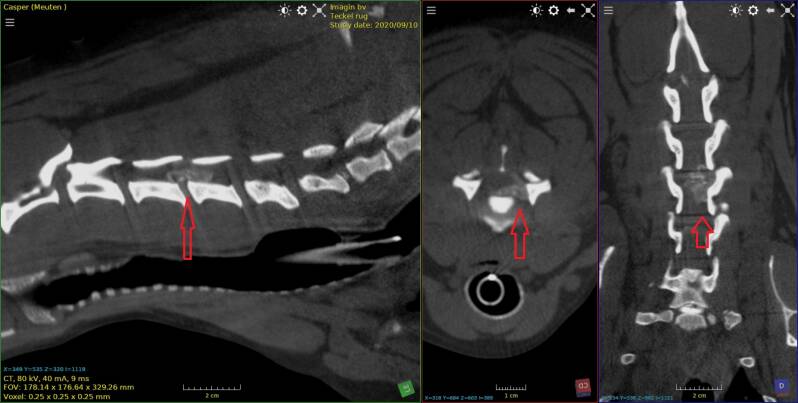

Teckel met discus hernia

Dalmatier van 11 jaar met verlamming ten gevolge van  discus hernia op de overgang van T13  naar L1.

Eerst beelden van RX,  daarna scan beelden met en zonder contrast , vervolgens 3D beeld.